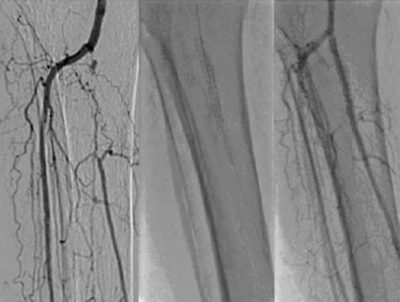

-  رابعا: “الدعامه الطرفيه للشرايين الدقيقه اسفل الركبه“

– تستخدم هذه الدعامه في الضيق الصعب او الانسدادات المركبه المرتجعه في شرايين اسفل الركبه

– تعتبر من التقنيات الحديثه التي تساعد علي علاج بعض الشرايين الدقيقه في حالات انسداد الشرايين الشديده